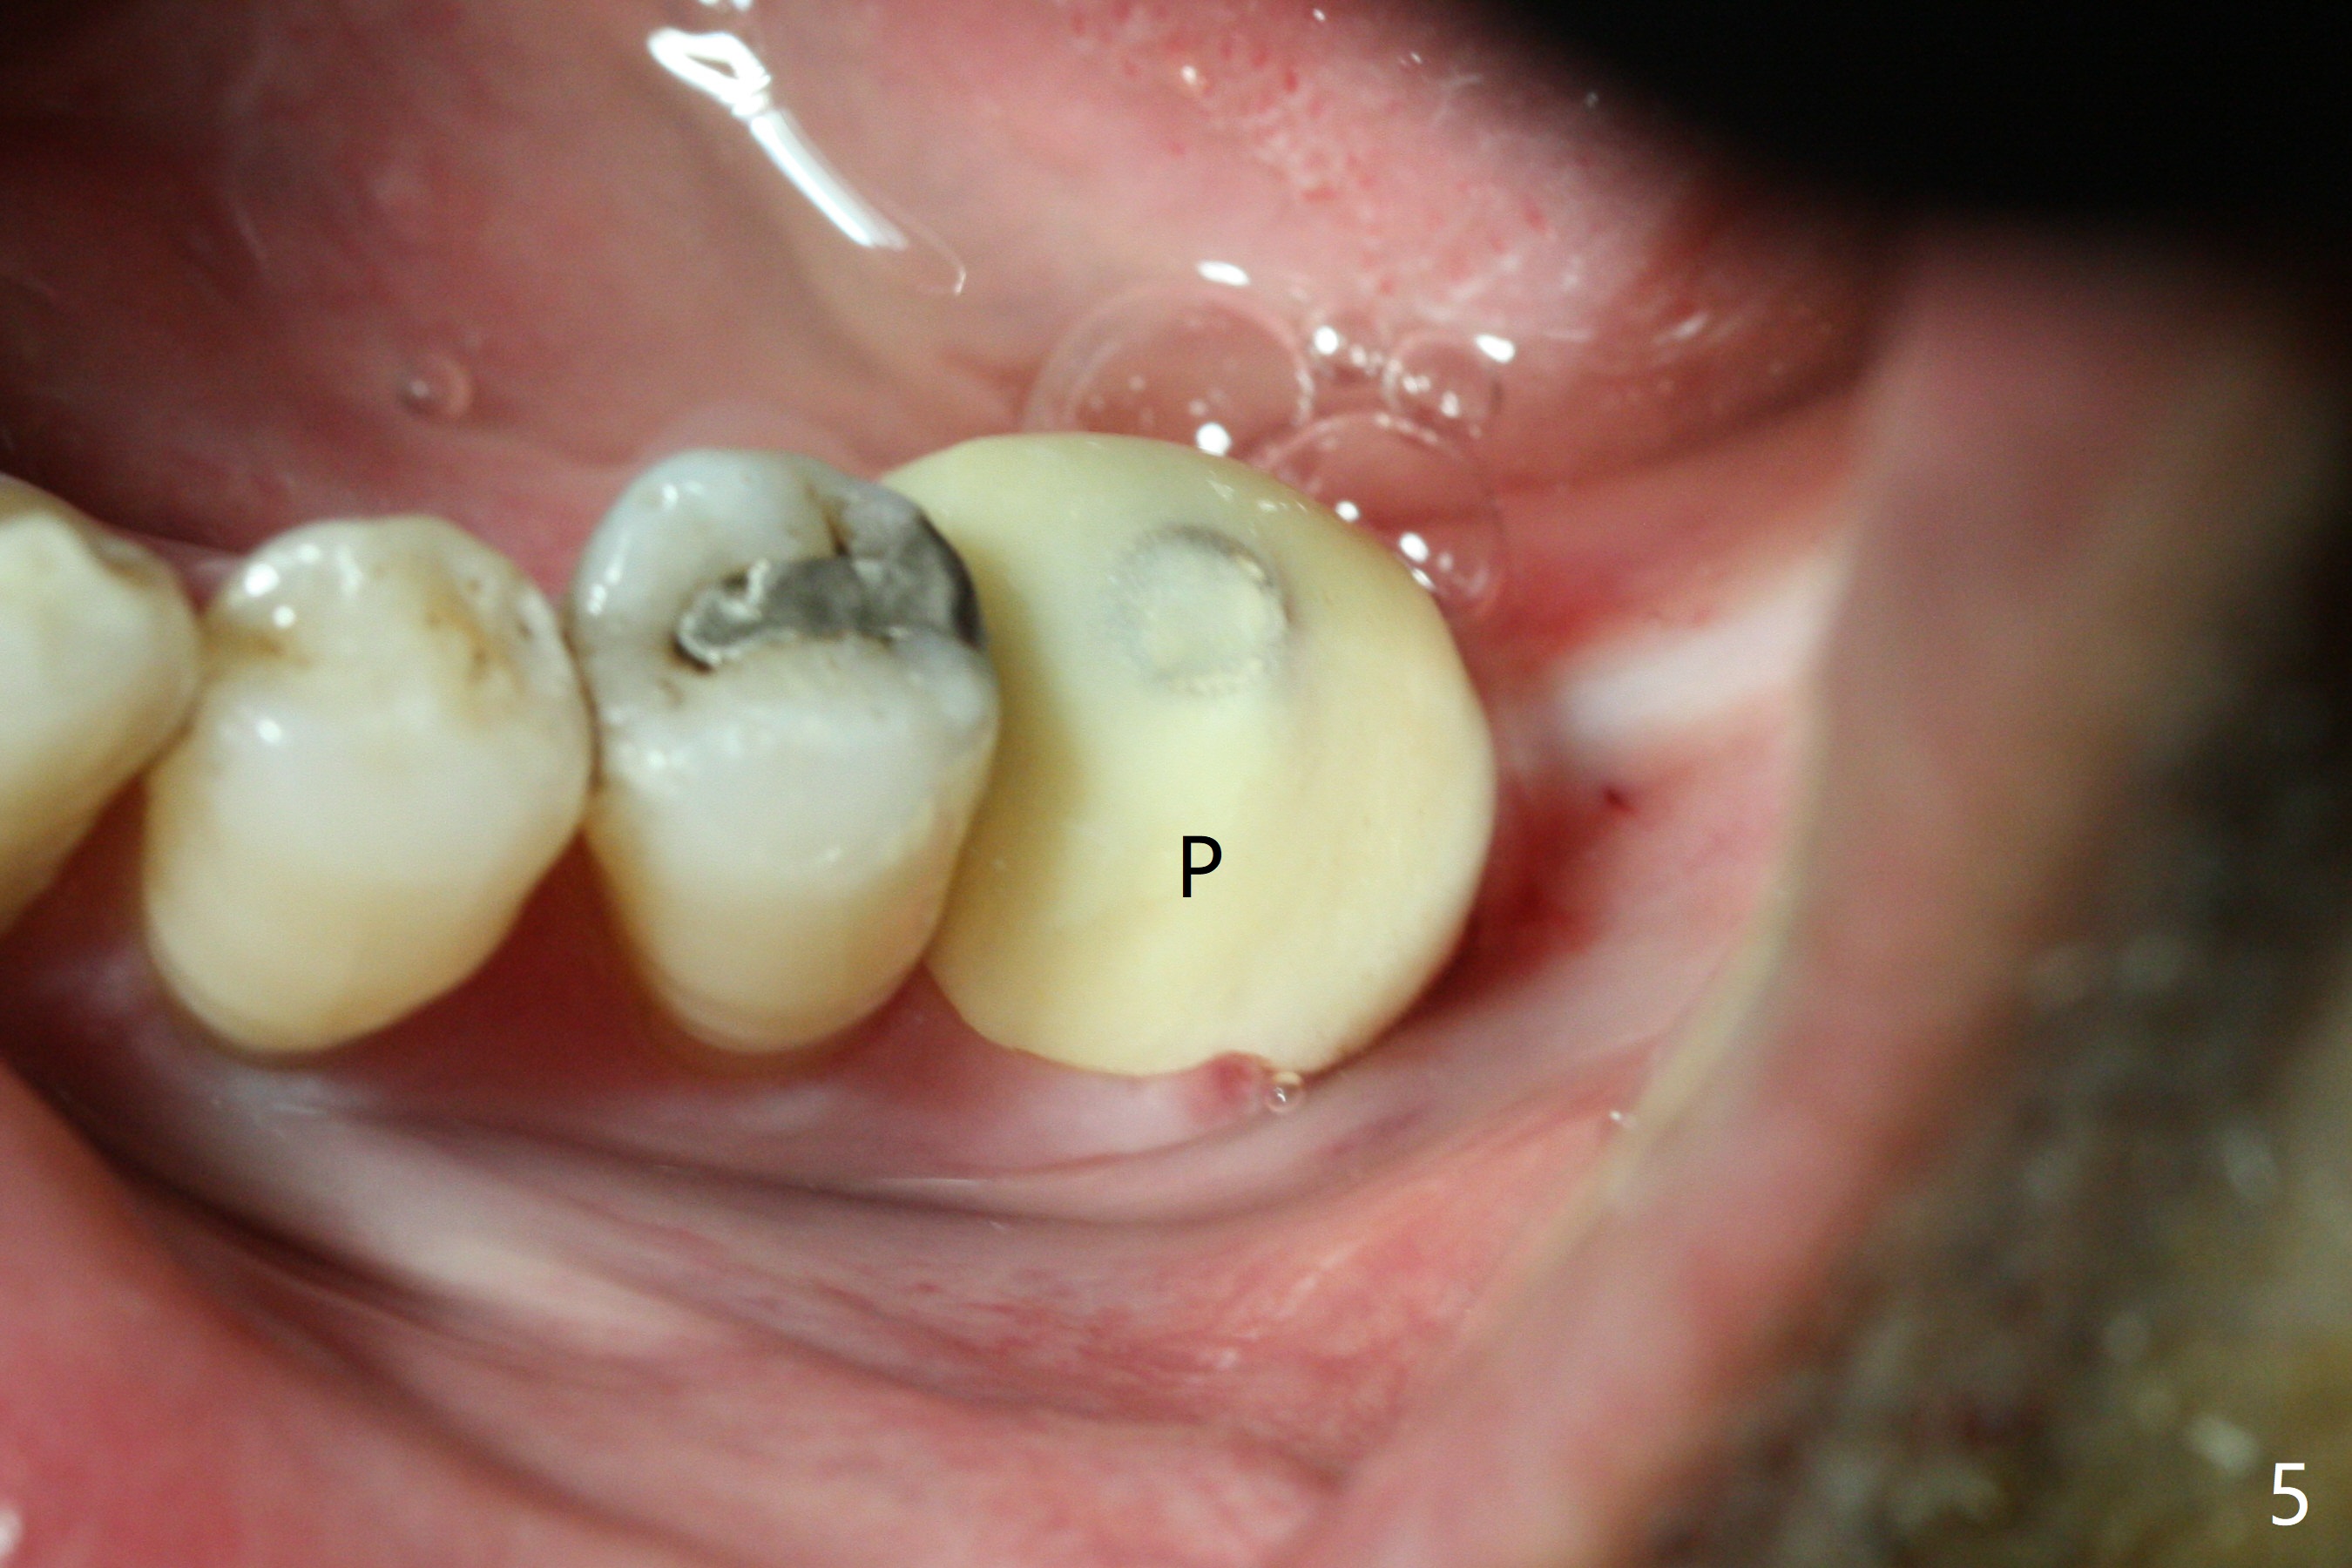

The guide does not arrive when the tooth #19 is extracted. Osteotomy is initiated free hand in the mesial socket as planned, slightly lingual, for 11.5 mm (Fig.1). Following sequential osteotomy, a 4.5x10 mm implant is placed subcrestal septally (Fig.2 S) and 2.3 mm from the neighboring apex (Fig.4). A 5.5x5(4) mm abutment is placed immediately and allograft is placed in the remaining sockets (Fig.4 *). An immediate provisional is fabricated to keep the graft in place (Fig.5 P; the most secure socket preservation).